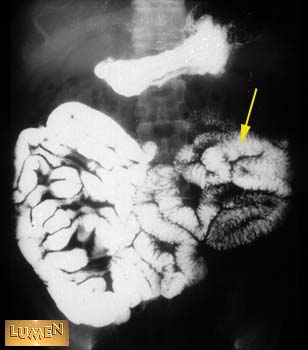

Question: Identify.

Jejunum.